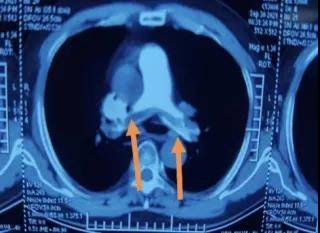

箭头指向 , 双侧肺动脉血栓位置

0:00 , 宫卫东主任为患者进行介入手术 , 首先下腔静脉+肺动脉造影 , 这进一步证实了 , 仁先生双肺动脉大面积栓塞 。 宫主任当即决定先植入下腔静脉滤器 , 为了预防下肢血栓再次脱落 , 加重肺栓塞 , 后在肺动脉血栓阻塞部分 , 进行血栓机械抽吸加溶栓治疗 。